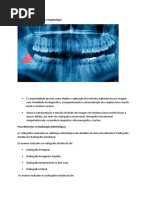

Os aparelhos de raios X odontológicos são utilizados para ex-

posição de receptores de imagem intrabucais ou extrabucais

(Figs. 01A,B). Aqueles utilizados para exposições intrabucais

são adaptáveis a qualquer tipo de receptor de imagem, seja

convencional (filme radiográfico), seja digital (placas de fósfo-

ro ou sensores de estado sólido). Os aparelhos utilizados para

exposições extrabucais são divididos em convencionais - que [B]

utilizam filmes radiográficos - e digitais - que utilizam sensores 01. [A,B] Aparelhos de raios X intrabucal

de estado sólido fixados do lado oposto à fonte de raios X. [A] e extrabucal - panorâmico digital [B].